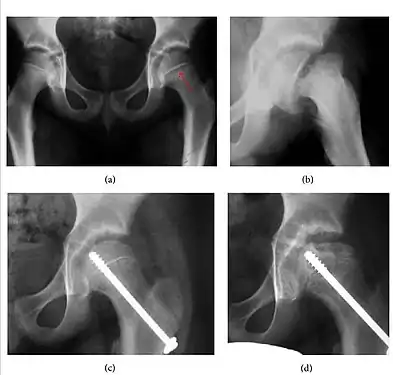

Figure 4: (a) X-ray of a 10-year-old child with left hip pain. It was considered normal at emergency despite the widening of the left physis (arrow). Two weeks later epiphysiolysis was evident (b). Despite appropriate surgical reduction (c) osteonecrosis developed and femoral head collapsed 1 month later (d).[1]